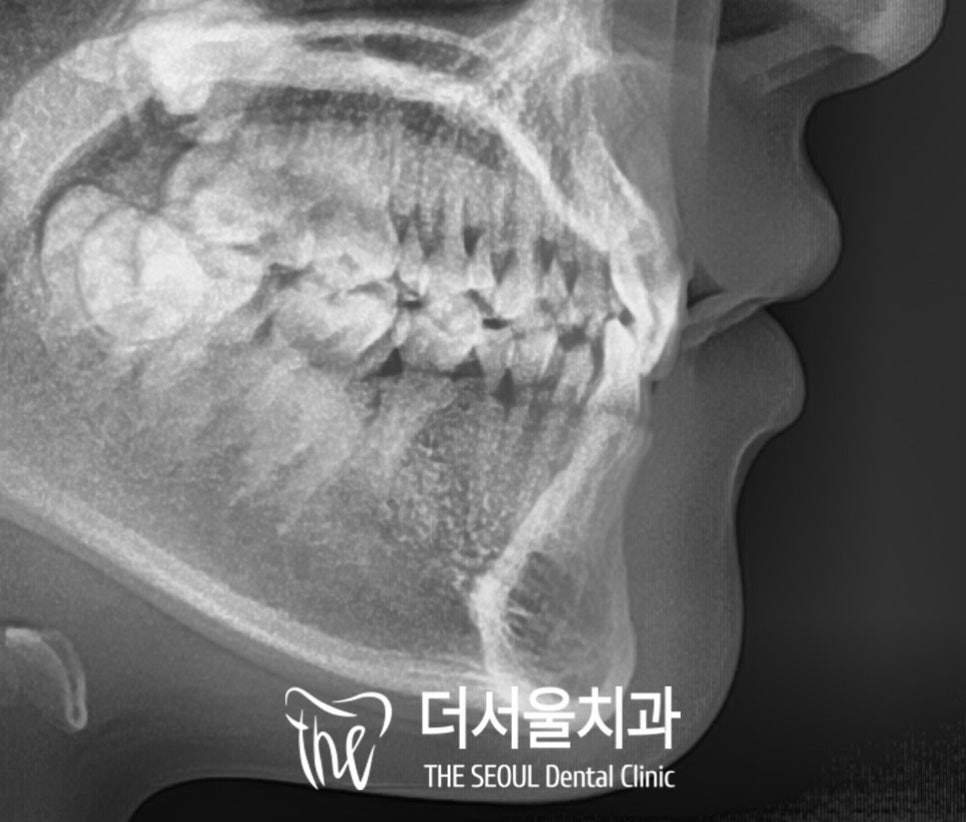

또한 옆모습을 방사선으로 관찰해보면

윗니가 아랫니를 3/4 이상 덮는

과개교합(딥바이트)을 하고 있고,